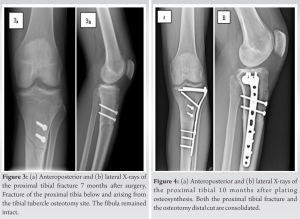

An emergency X-ray of the knee confirmed a spontaneous fracture of the proximal tibia below and arising from the TTO site. The fibula remained intact (Fig. 3). A plating osteosynthesis of the proximal tibia was carried out to avoid cast immobilization and to maintain knee’s function (Fig. 4). Weight-bearing was completely prohibited for 8 weeks while the range of motion was gradually recovered and completed after 2 weeks. A removable knee extension splint and 2 crutches protected the osteosynthesis for 8 weeks. Full weight-bearing and normal gait were obtained at 3 months. Both the proximal tibial fracture and the osteotomy distal cut were consolidated at 10 months after plating osteosynthesis (Fig. 4). KOOS score was, at that time, evaluated at 90.5.